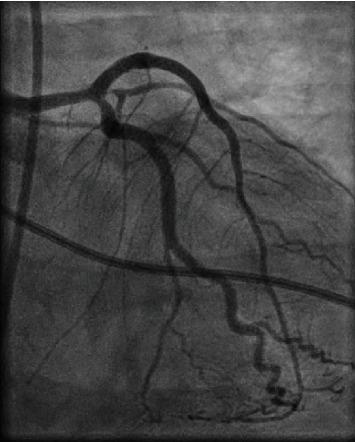

Both COVID-19 disease and cocaine consumption have prothrombotic and hypercoagulable effects and are associated with increased risk of cardiovascular events. We report the case of a patient with acute myocardial infarction in the setting of active COVID-19 disease and recent cocaine consumption. We hypothesize that COVID-19 and cocaine synergistically provoke cardiovascular events. Identifying COVID-19 disease and/or cocaine abuse as potential triggers of acute myocardial infarction can be crucial due to distinctive therapeutic consequences.

新冠病毒疾病和可卡因使用均具有促血栓形成和高凝作用,并与心血管事件风险增加相关。我们报告了一例在患有活动性新冠病毒疾病且近期使用过可卡因的情况下发生急性心肌梗死的患者。我们推测新冠病毒疾病和可卡因会协同引发心血管事件。鉴于独特的治疗后果,将新冠病毒疾病和/或可卡因滥用识别为急性心肌梗死的潜在触发因素可能至关重要。